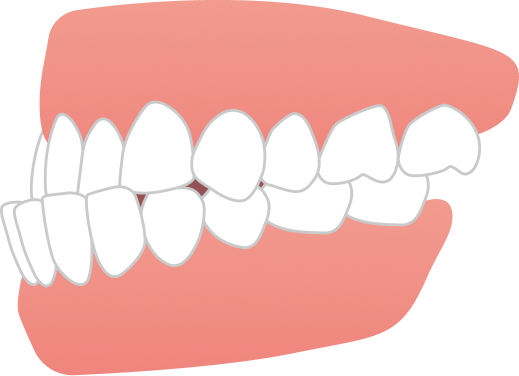

治療期間は1年8ヶ月で、大学生のうちに治療を終えることができました。見た目の改善だけでなく、噛み合わせも整い、前歯でしっかり噛めるようになっています。

AFTER

| 施術内容 | 歯全体のマウスピース矯正システム「インビザラインフル」を用いた治療 |

| 治療期間 | 1年8ヶ月 |